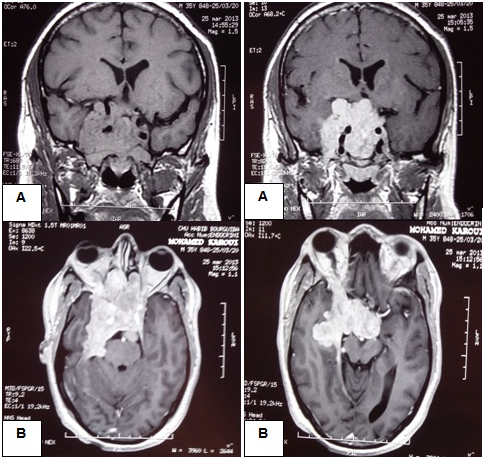

A 40-year-old male complained of right proptosis, intermittent unilateral nasal obstruction and headaches that had persisted for 3 months. He had no previous history of trauma. He was admitted to the ENT department. Ophtalmological examination showed a reductible axial right-sided exophtalmos. The patient had no neurological deficits. The nasal endoscopy found a large submucosal bulging on the superior and posterior wall of the nasopharynx which infiltrates the posterior part of the nasal septum. Cerebral tomodensitometry showed a large tumoral mass of the skull base which invades the sellar and parasellar region, the chiasm region, the right middle cranial fossa and extends into the rear face of the petrous bone with osteolysis of the sphenoid. The nasopharynx biopsy found a reactive benigne lymphoid hyperplasia of the nasopharynx mucosa. MRI revealed a heterogenous pituitary giant adenoma of 84*68*64 mm in diameter, isointense to grey matter on T1, hyperintense on T2 and enhanced strongly after injection of Gadolinium. The tumour extended into the nasal cavity and the right orbit, invading the optic canal and the superior orbital fissure with a right exophtalmos grade III (Figure 1).

Based on the serum PRL levels and the imaging appearances, the diagnosis of an invasive giant prolactinoma was made and the patient was started on treatment. BRC was initially administred at a dose of 1.25 mg/day and progressively increased to a total dose of 7.5 mg/day. Three months after bromocriptine therapy initiation, PRL levels were reduced to 41 078 ng/mL with improvement of the exophtalmos. Follow-up imaging showed moderate shrinkage of the tumour (66*42 mm).

As in macroprolactinomas, Dopamine Agonist (DA) therapy is the primary treatment for giant prolactinomas as it has been proved to be effective in reducing PRL levels and inducing significant tumour shrinkage.1,2,14,15 In contrast to the time required to reduce PRL levels and tumour size, the effect of DA on visual disorders is rapidely apparent within days after initiation of the treatment.2 There are several reports of rapid resolution under medical treatment alone of proptosis induced by giant prolactinomas.8,9,16 These effects were also observed with our patient who showed a remarkably good response to BRC with reduction of proptosis, reduction in PRL levels and moderate shrinkage of the tumour on a 3 month follow-up MRI.